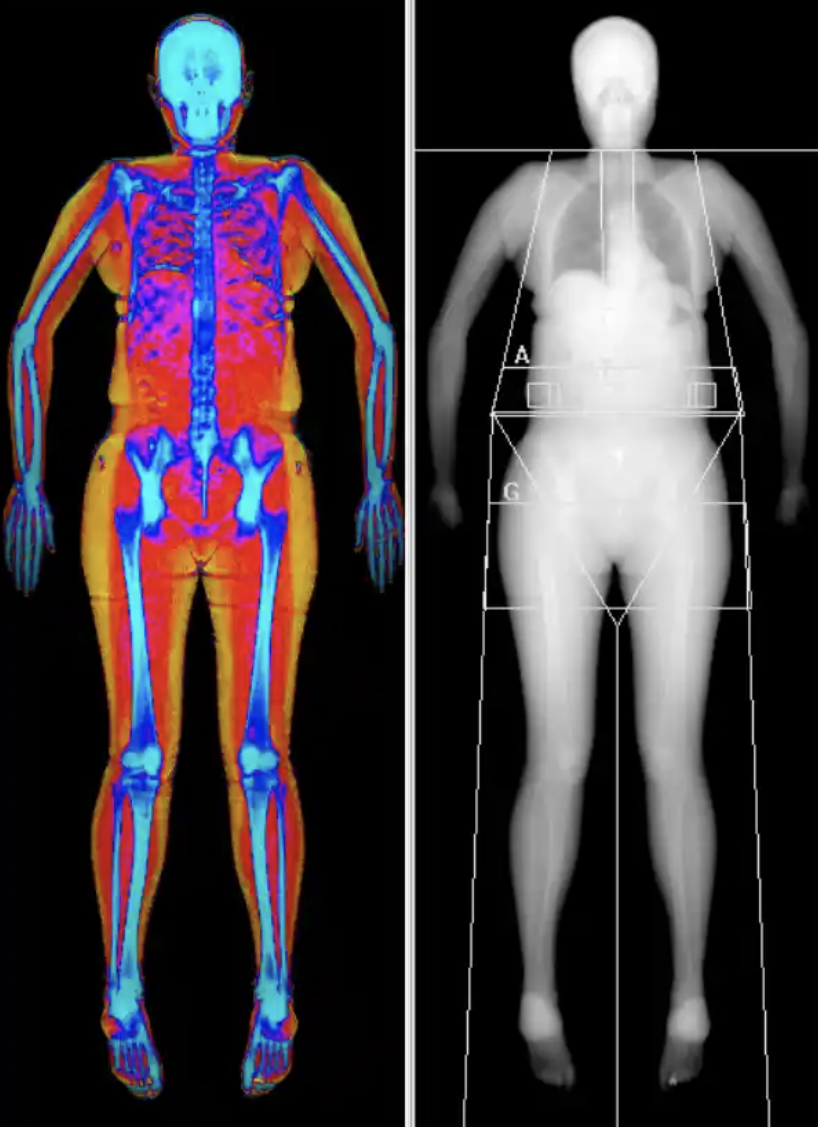

MRI Full body Plus

MRI + blood tests

- Radiation-free whole-body MRI examination.

- 50+ blood tests for an extended medical overview.

- Early detection of risks and diseases.

MRI Full Body Pro

MRI + blood tests + ECG

- Full body MRI scan.

- 70+ blood tests incl. biological age.

- Long-term ECG 5–7 days with ePatch.

MRI Full Body

Magnetic resonance imaging

- Magnetic camera examination of the full body

- Recommended for those who are healthy for screening purposes

- Detailed examination with magnetic camera

- MRI full body, referral sent directly